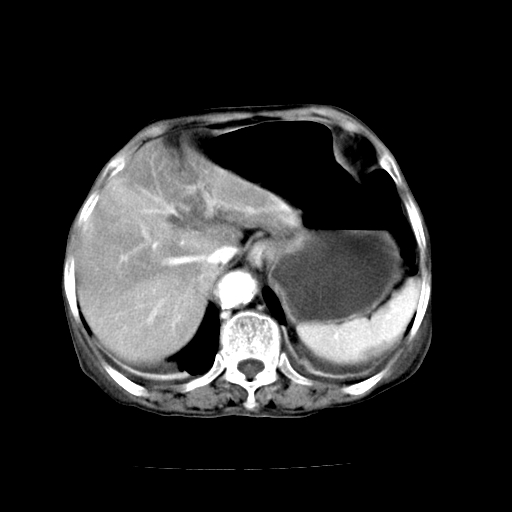

标题: CT19149:女,68岁,腹胀、恶心两周。 [打印本页]

女,68岁,腹胀、恶心两周,先做ct平扫,当时家属不同意强化,6天后家属要求增强扫描。